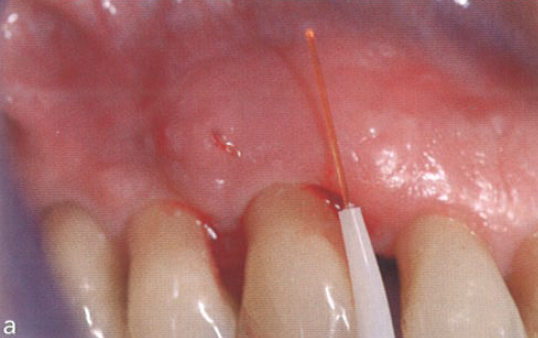

临床医师将大量具有致病性的病原菌的生物膜去除,从而阻断了由菌斑诱导的牙周炎症的复发。除了让患者在家中遵循更有效的清洁程序外,还建议使用半导体激光(图2)。

口腔激光怎么治疗“难治性”牙周炎的激光辅助治疗_https://www.jmylbn.com_新闻资讯_第4张

图2  使用半导体激光处理牙周

使用该半导体激光的目的是杀菌,并与常规的牙周非手术刮治相结合。在4个月后的随访复诊中,用轻柔的力量进行探诊,探诊深度稳定在大约5 mm,无探诊出血。